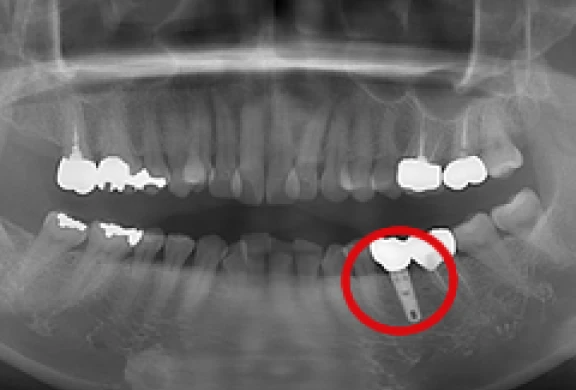

上部構造の装着

-

パノラマ

歯間部のインプラント

(上部構造の装着)